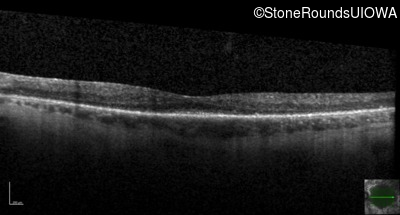

Optical Coherence Tomography - Left - 20/40 +1

Exemplar / OCT Stack

OCT Stack